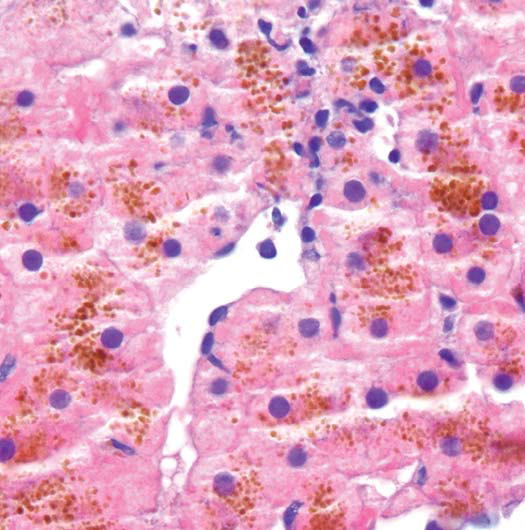

Below is feathery degeneration - demaged hepatocytes with 1. hydropic swelling 2.diffuse impregnation with bile pigment 3. reticulated appearance.